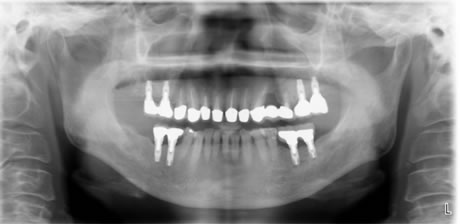

治療後のレントゲン、口腔内写真です。

奥歯すべてにインプラント治療を行いました。歯周基本治療をおこない歯肉の発赤もなく、PCR20パーセント以下、BOP9パーセント以下です。

綺麗な口腔内になりました。

After

このあともインプラント周囲炎にならないようにメインテナンスに来院していただきます。